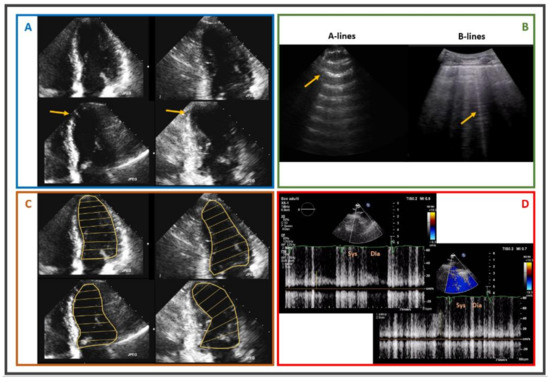

- Picano, E.; Ciampi, Q.; Wierzbowska-Drabik, K.; Urluescu, M.L.; Morrone, D.; Carpeggiani, C. The new clinical standard of integrated quadruple stress echocardiography with ABCD protocol. Cardiovasc. Ultrasound 2018, 16, 22. [Google Scholar] [CrossRef]

- Picano, E.; Zagatina, A.; Wierzbowska-Drabik, K.; Borguezan Daros, C.; D’Andrea, A.; Ciampi, Q. Sustainability and Versatility of the ABCDE Protocol for Stress Echocardiography. J. Clin. Med. 2020, 9, 3184. [Google Scholar] [CrossRef]

- Ciampi, Q.; Zagatina, A.; Cortigiani, L.; Wierzbowska-Drabik, K.; Kasprzak, J.D.; Haberka, M.; Djordjevic-Dikic, A.; Beleslin, B.; Boshchenko, A.; Ryabova, T.; et al. Prognostic value of stress echocardiography assessed by the ABCDE protocol. Eur. Heart J. 2021, 42, 3869–3878. [Google Scholar] [CrossRef]